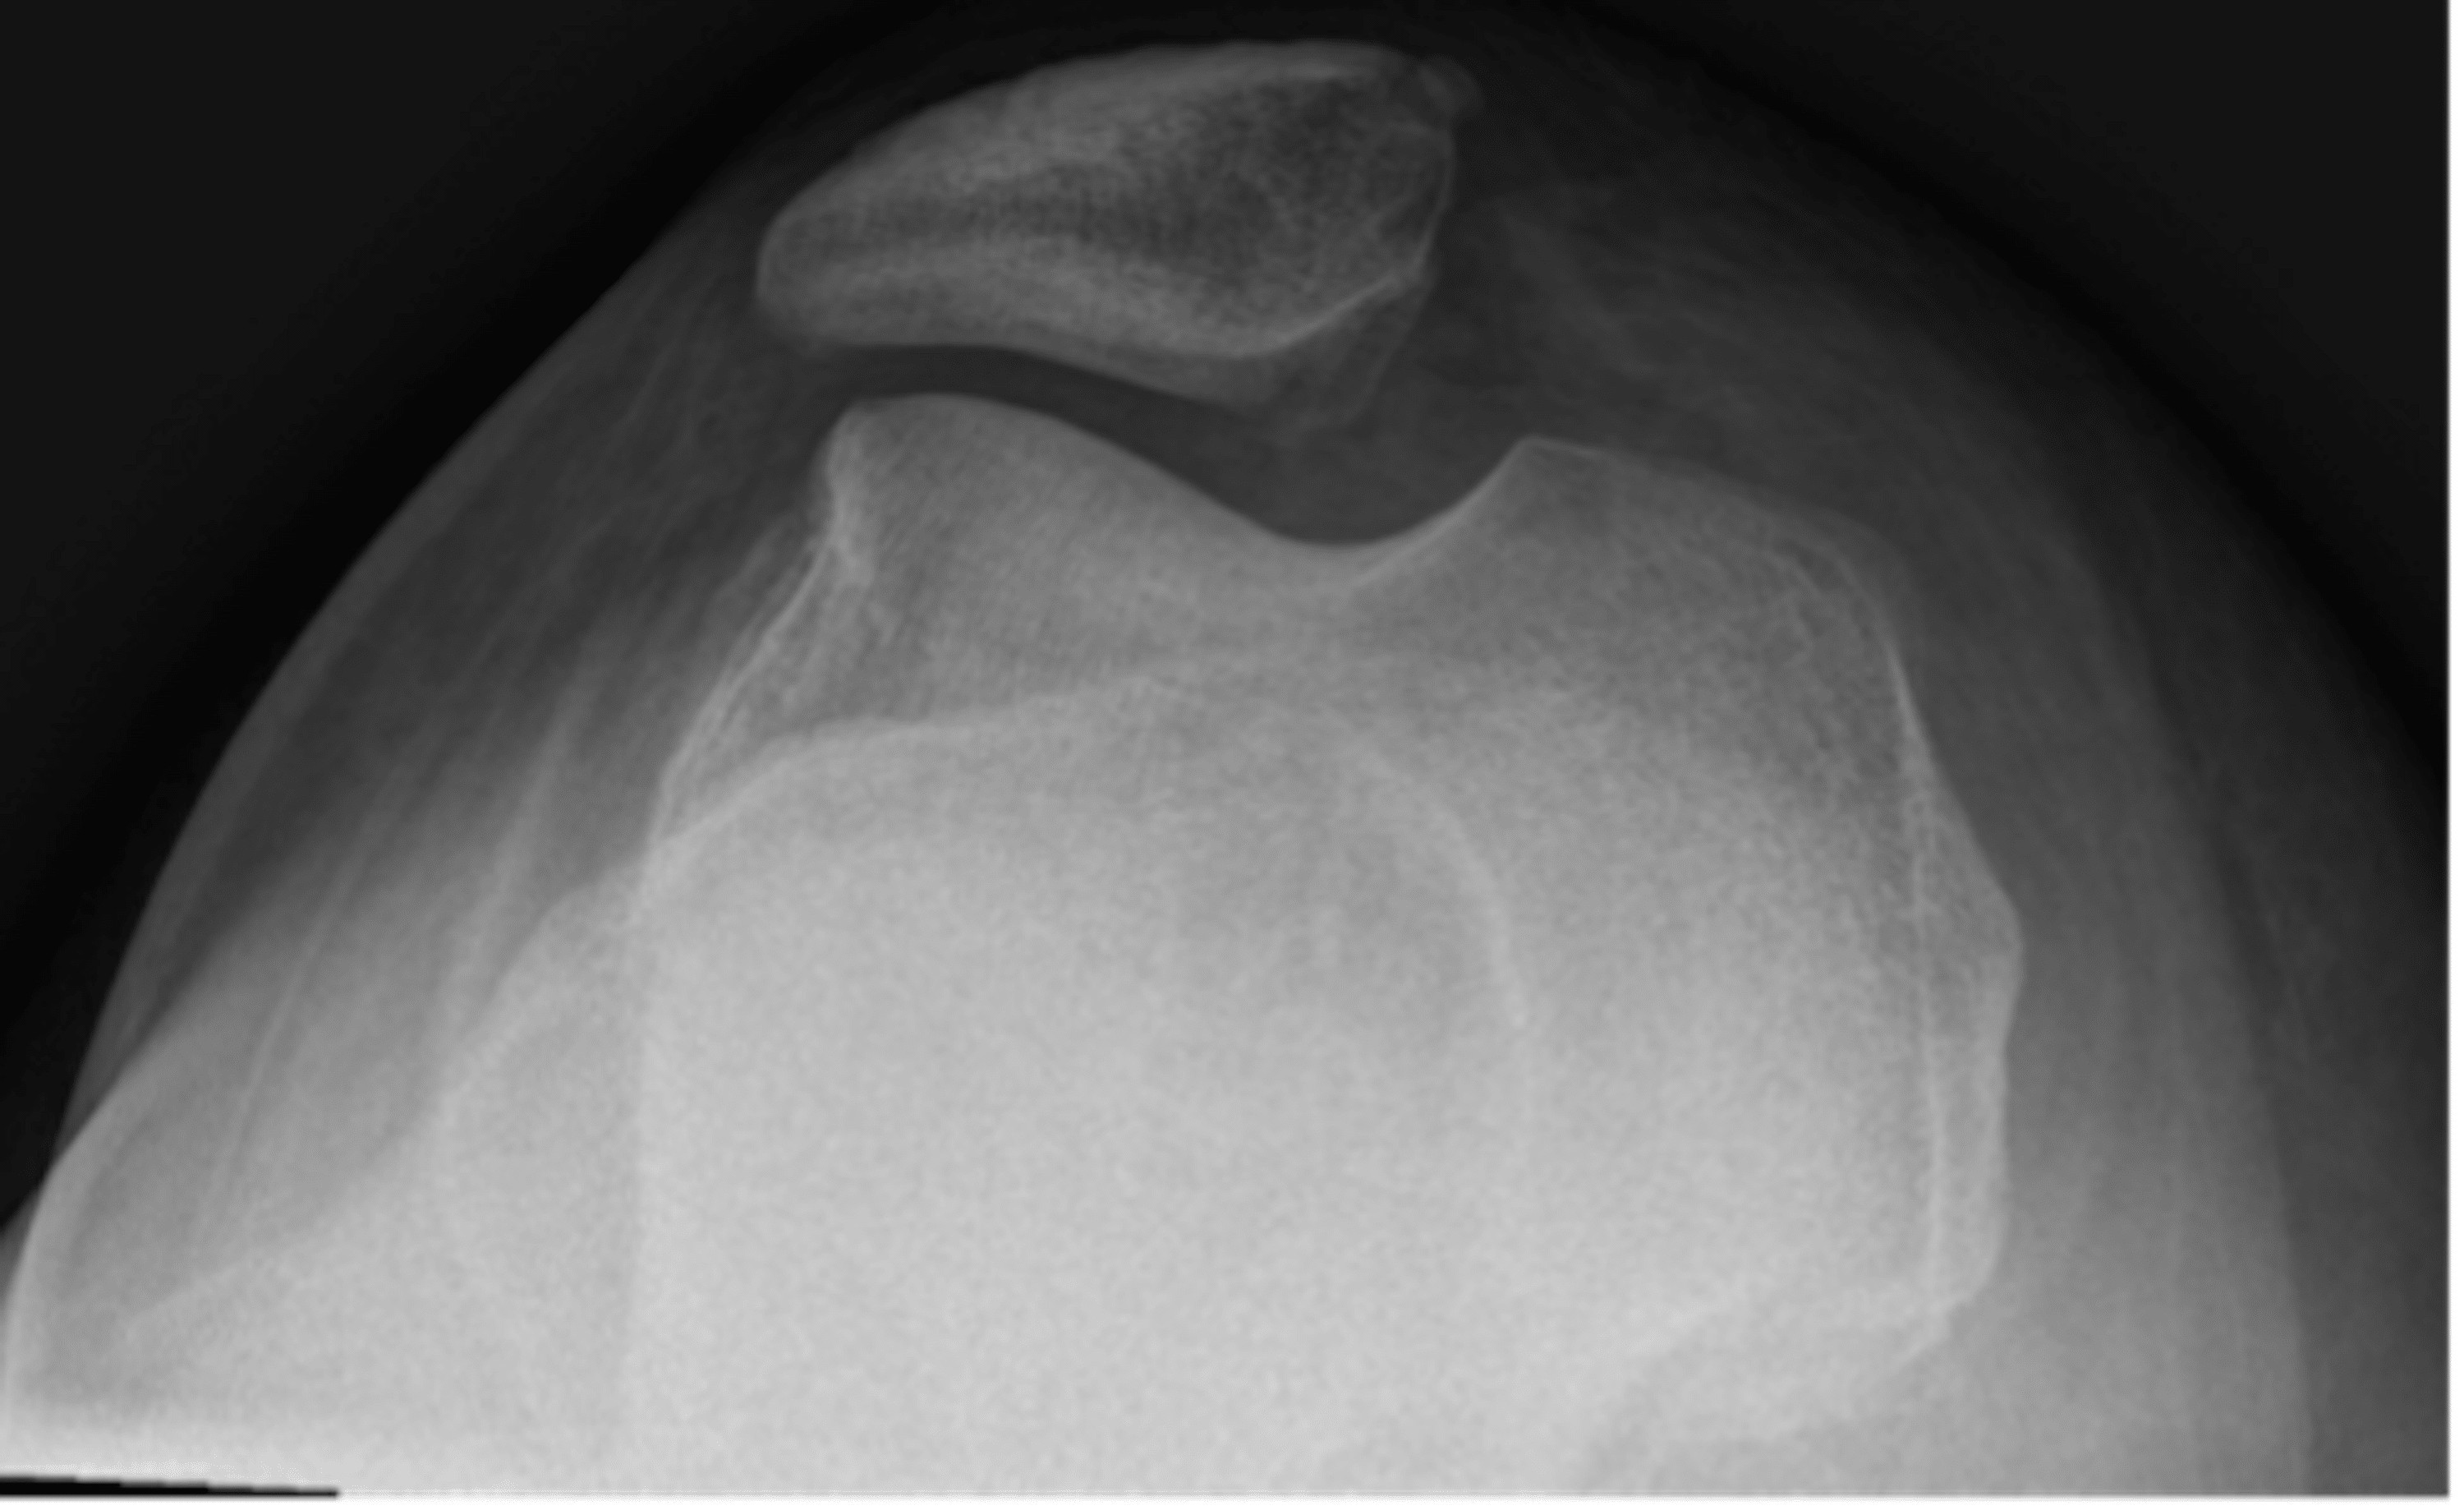

From www.jem-journal.com

Closed Emergency Department Reduction of a Superior Patellar Locked Knee Reduction It can be classified as acute or. knee locking is where the knee gets stuck and can't bend or straighten. most cases of a locked knee do not require surgery but effective treatment depends on accurate diagnosis. You might feel like your knee is popping or catching when you try to move your leg, or that it buckles. Locked Knee Reduction.